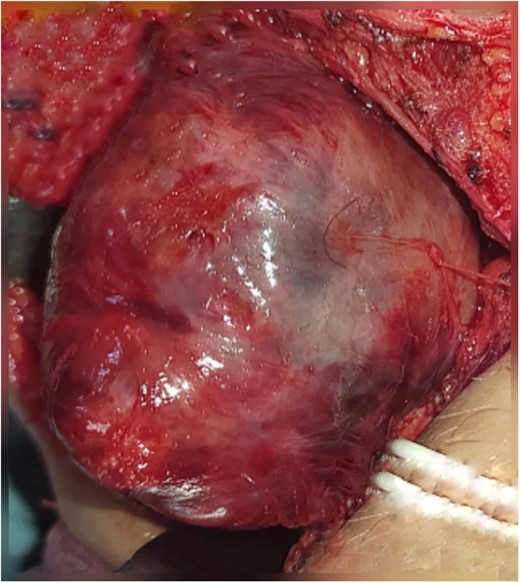

Excision of the tumor was principally done by a combined route. The first incision is a 10-cm external incision made below the arch of the left mandible from the mastoid tip to the neck middle; after flap elevation, the tumor was exposed but enucleation attempts were not successful due to its large volume, which forced us to make a second endo-buccal incision that was 5 cm in size and performed on the anterior tonsil pillar (Palatoglossal arch); this access was used to enucleate the rest of the tumor and thus its total detachment. The tumor was a well-circumscribed, homogeneous and lobulated firm red mass (Fig. 2). The wound was closed in layers with drain in situ.